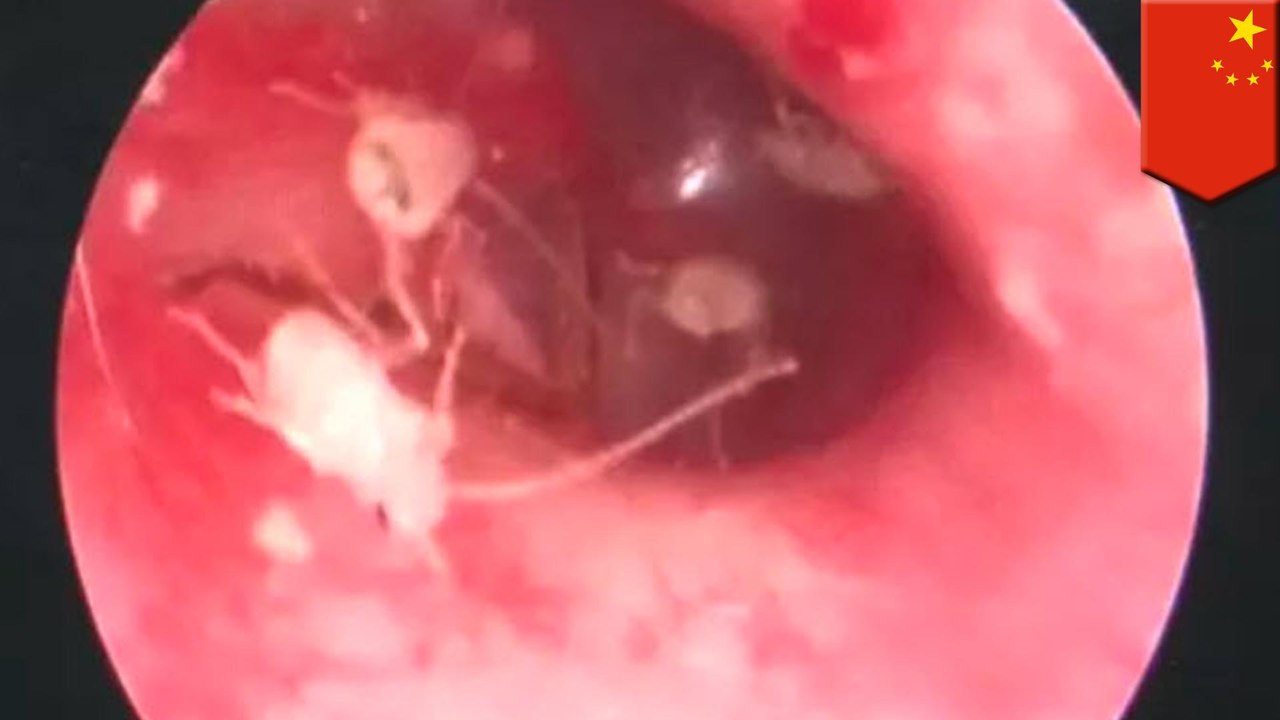

Doctor pulls live cockroach from man's ear

A doctor pulled a two-centimetre-long cockroach out of a man's ear in southern China.<br /><br />In the clip, captured in Shenzhen City in Guangdong Province on June 15, a cockroach can be seen in the ear of a man only named Li through an otoscope.<br /><br />The doctor uses a pair of tweezers to pull it out slowly.<br /><br />One of Li's relative is shocked and can be heard saying: "Cockroach? Are you sure it is a cockroach?"<br /><br />Another video shows how the dismembered cockroach is still moving between the tweezers.<br /><br />According to reports, it climbed into Li's ear when he was sleeping.